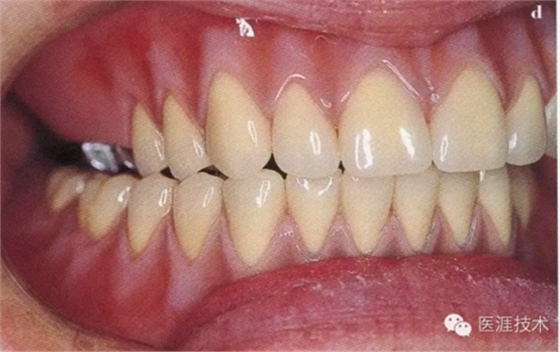

23,制作完成義齒口腔內(nèi)狀態(tài)

24,術(shù)前術(shù)后對(duì)比

患者對(duì)最終治療效果非常滿意,不僅恢復(fù)了咀嚼能力,而且還改善了全身健康狀態(tài)和精神狀態(tài)。

患者最大的感受是在拔牙后,患者在整個(gè)口腔組織恢復(fù)過(guò)程中就已經(jīng)開(kāi)始佩戴義齒,通過(guò)6個(gè)月的適應(yīng)后,患者對(duì)義齒的佩戴已經(jīng)十分習(xí)慣,這點(diǎn)加倍了患者滿意程度。